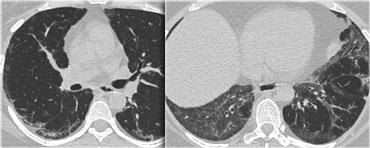

Bệnh nhân này nhập viện với triệu chứng khó thở cấp tính và phim X-quang ngực bình thường (không trình bày).

HRCT lúc nhập viện (trái) cho thấy các vùng kính mờ theo phân bố tiểu thùy.

HRCT kiểm tra mười ngày sau (phải) cho thấy các tổn thương đã thoái lui hoàn toàn mà không cần điều trị.

Các tổn thương được cho là do viêm phổi quá mẫn.